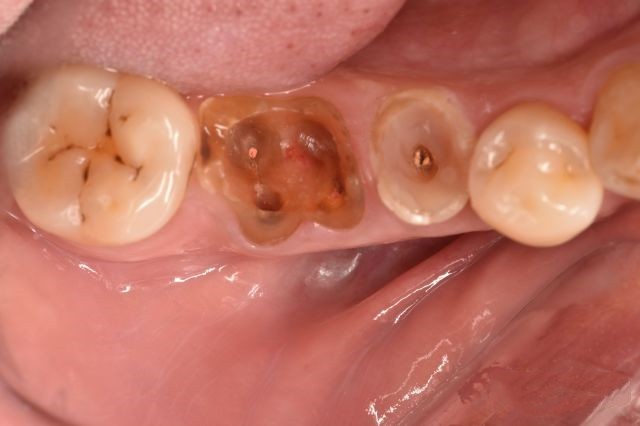

先给大家看一张牙周情况糟糕的图片。

从图片就能看出,这位34岁的男子牙周情况很差—— 牙结石积多,牙龈红肿发炎,牙齿松动,牙根暴露。

经过牙周治疗,牙周恢复到稳定状态后,我院正畸一科狄耀云医生才对其进行矫正。